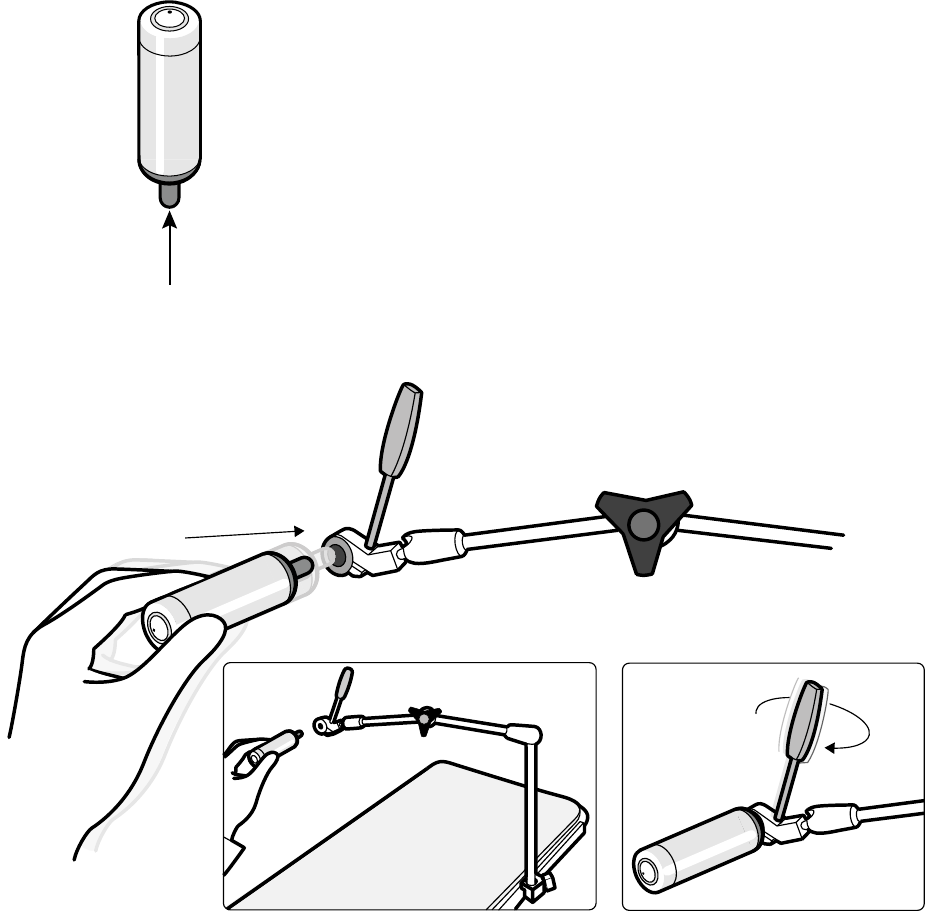

11.17 Narzędzie laserowe XperGuide (opcja)................................................................................ 203

11.17.1 Włączanie i wyłączanie narzędzia laserowego XperGuide................................... 204

11.17.2 Ładowanie narzędzia laserowego XperGuide...................................................... 205